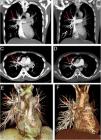

A 40-year-old male with Behcet's disease presented with complaints of cough, dyspnea, and intermittent hemoptysis. Maximum intensity projection (MIP) thorax computed tomography (CT) angiography scans revealed aneurysms in the anterior and posterior segmentary pulmonary arteries of the right upper lobe (Fig. 1A and C). Corticosteroids and intravenous cyclophosphamide treatment was applied to the patient. In control examination after eight months, thorax CT angiography scans showed complete resolution of the aneurysm in the posterior segmentary pulmonary artery of the right upper lobe (Fig. 1B and D). Aneurysm in the anterior segmentary pulmonary artery showed persistently in CT angiographic images. In presentation and control examination, anterior view 3D volume rendering CT images revealed clearly persistent and shrinking aneurysms (Fig. 1E and F).

In presentation, coronal (A) and axial (C) MIP thorax CT angiography scans reveal aneurysms in the anterior (frame) and posterior (arrow) segmentary pulmonary arteries of the right upper lobe. In control examination eight months after corticosteroid and intravenous cyclophosphamide treatment, coronal (B) and axial (D) MIP thorax CT angiography scans show complete resolution (arrow) of the aneurysm in the posterior segmentary pulmonary artery of the right upper lobe. Aneurysm (frame) in the anterior segmentary pulmonary artery shows persistently in CT angiographic images. In presentation (E) and control examination (F), anterior view 3D volume rendering CT images reveal clearly persistent (asterisk) and shrinking (arrow) aneurysms.